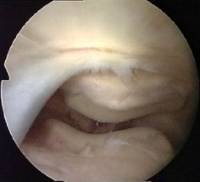

A suprapatellar plica may stretch right across the suprapatellar pouch, dividing it into two. This is called a 'complete septum', and its presence may confuse a novice arthroscopist. It is easier for you to understand a complete septum if you see an almost complete one - what we call a 'fenestrated' plica. That means 'a plica with a window'.